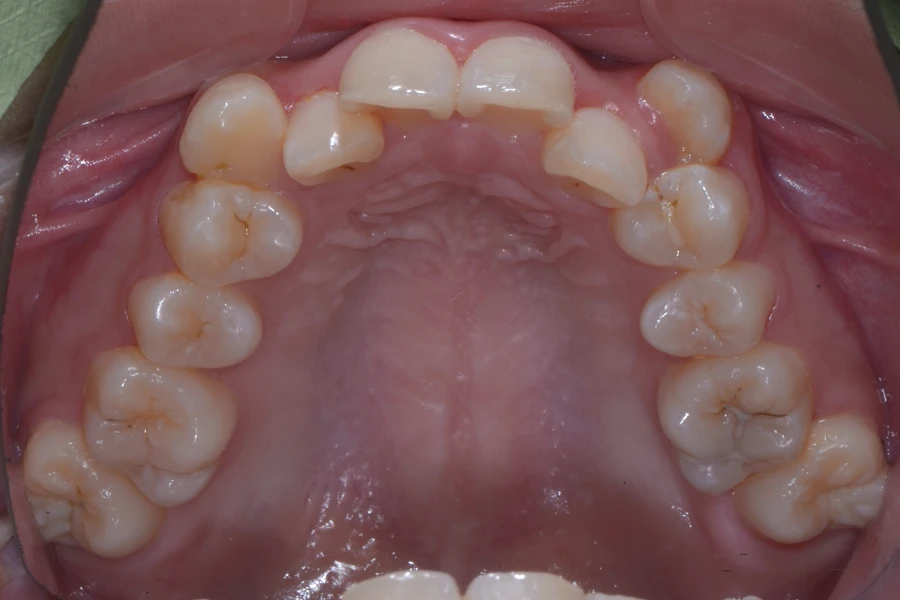

• 治療後

主訴 八重歯を治したい

期間 12か月

費用 40万円(別途調整料)

治療内容 上下顎ラビアル矯正(表側矯正)